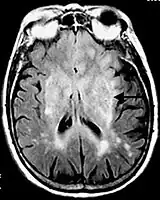

![]() Postcontrast FLAIR of a case of meningitis. It shows enhancement of meninges at the tentorium and in the parietal region, with evidence of dilated ventricles. |

Fluid-attenuated inversion recovery (FLAIR) is an MRI sequence with an inversion recovery set to null fluids. For example, it can be used in brain imaging to suppress cerebrospinal fluid (CSF) effects on the image, so as to bring out the periventricular hyperintense lesions, such as multiple sclerosis (MS) plaques.[1] It was invented by Dr. Graeme Bydder. FLAIR can be used with both three-dimensional imaging (3D FLAIR) or two dimensional imaging (2D FLAIR).

The FLAIR sequence analysis has been especially useful in the evaluation and study of CNS disorders, involving:[2]

- Meningitis and other leptomeningeal diseases*

* Post-contrast FLAIR images have been added to diagnosis protocol for accurate medical assessment.[2]